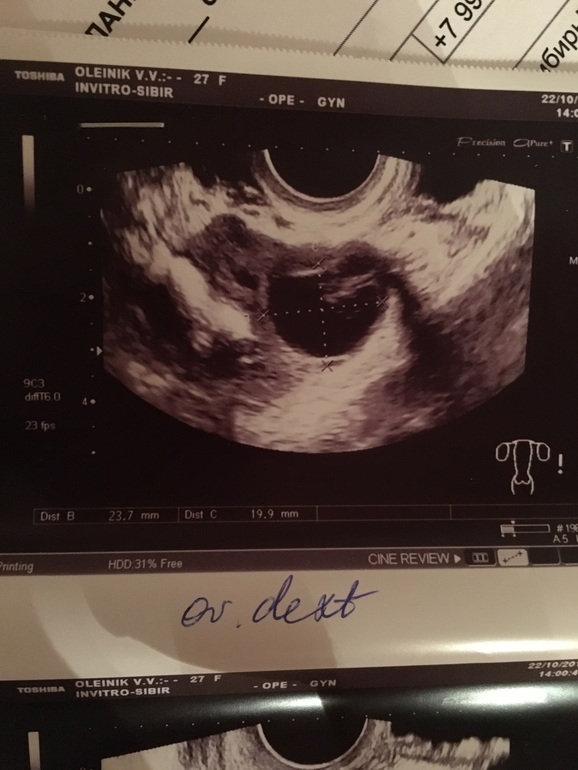

Это на 14 дц узи

У вас был доминантный фолликул на 14ДЦ, дальше должна была быть О, но по какой-то причине что-то пошло не так и ЖТ получилось с кровотоком. Т.е не совершенное, не как при О. Могу предположить, что фоллик перерос и не смог лопнуть. Вот вам и описали ЖТ с кровотоком и диаметром приблизительно вашего фолика, отсюда и тонкий эндометрий, потому что ЖТ не работает. Ничего ужасного, но в этом цикле Б быть не может.

А мне кажется у вас всё нормально! Ничего страшного в узи не вижу. Эндик нормальный, О была. Я конечно не узист, но и узисты иногда попадаются не очень. К врачу лучше сходить и уже всё выяснить

Да лучше сходите. Эндик вопросы вызывает и недостаточность второй фазы.